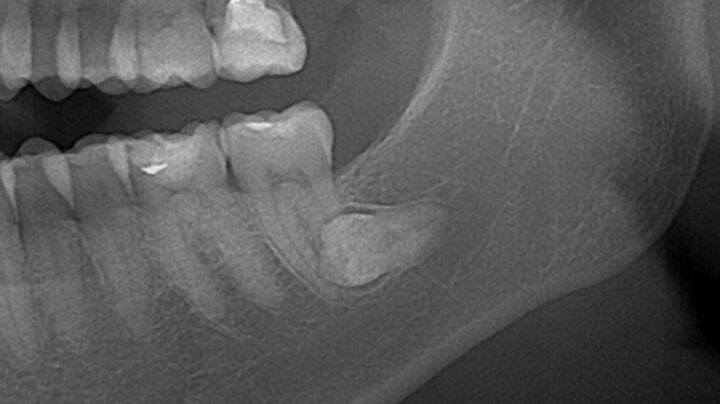

下の親知らずは上の親知らずに比べ、歯の周りの骨が硬く、歯茎や骨の中に埋まっていることも多いため、場合によっては歯茎の切開、骨を削る、歯の分割などの大掛かりな行程が必要なケースがあります。

そのため、抜歯後の痛みや腫れも上の親知らずに比べ大きく、1〜2週間程症状が続くこともあります。

下の親知らずの抜歯のリスクのひとつに「下歯槽神経の損傷」があります。

下の親知らずは個人差もありますが下歯槽神経という神経に近く、抜歯することで下歯槽神経が損傷してしまうことがあります。

そのため歯科医師は、通常のレントゲンである程度の歯と神経との距離を確認し、レントゲンで見て歯と神経が近い場合や、距離関係がわかりづらい場合はCTを撮影し正確な位置を確認することがあります。